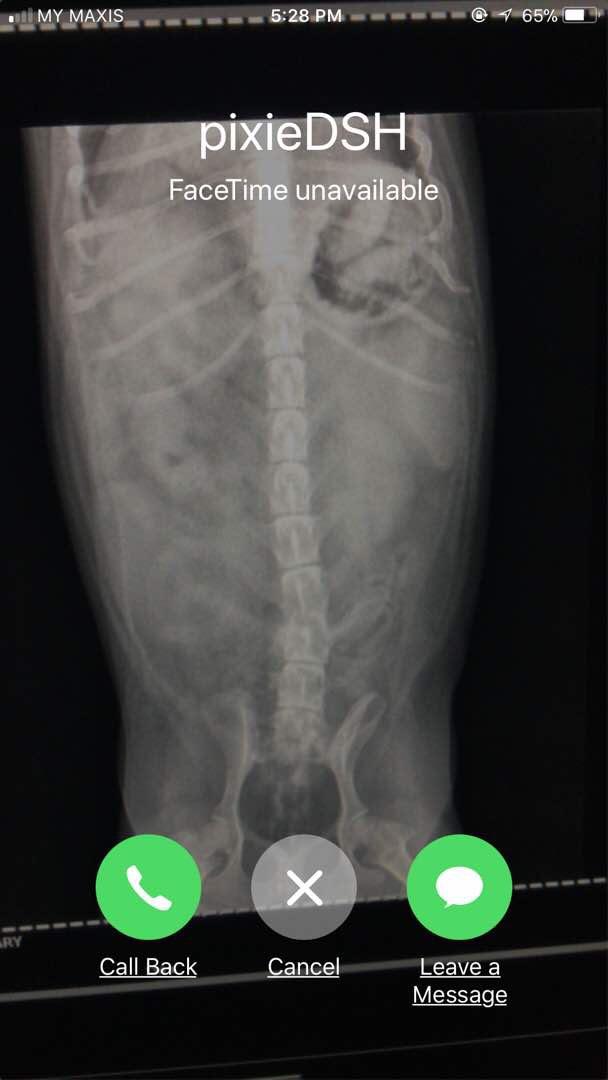

My 7-year old male dachshund is having bloody stool for the last 2 days, today went for X-ray and the vet couldn't indicate what is in his stomach and whether is a serious matter. Sincerely need your precious advice, I'm so worried now.

Hi there and thank you for using pet coach to address your concern. The x-rays that you provided show what looks to be foreign material in the stomach. It looks very similar to pieces of a ball with the rounded edges. This does not appear to be ingested food based on the appearance and shape period while not serious at the moment, one of these could pass from the stomach into the intestines and cause serious problems. I would consider rechecking the X-ray a few hours after the previous x-rays have been taken to see if there has been any change in the pattern. If there is no change in the pattern, I would suggest taking pixie in for surgery to have the abdomen explored. Prior to the surgery, you can also have an abdominal ultrasound performed to help confirm foreign material in the stomach. I hope this helps guide you in the right direction. Please feel free to contact you any other questions or concerns you may have